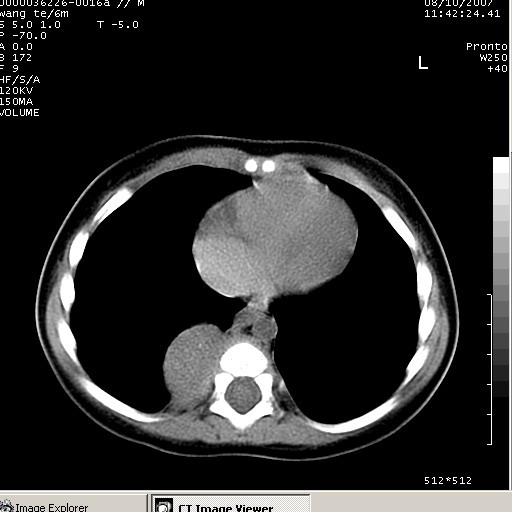

患儿男、6个月,因咳嗽三天曾拍胸片考虑肺部感染,这是在胸片后约一周左右作的ct。

右下肺纵隔旁软组织密度影,边界清楚,内见点状高密度影。支持考虑:神经源性肿瘤!

右下肺纵隔旁软组织密度影,宽基底紧贴胸椎与肋骨,边界清楚,内见点状高密度影。支持考虑:神经源性肿瘤!肺隔离症待排

右下肺纵隔旁软组织密度影,边界清楚,考虑神经源性肿瘤。

图有点少,但能看出越往下似乎越大,我认为除了考虑神经源性肿瘤,还要考虑膈疝可能

右下肺纵隔旁边界清楚软组织密度影,内见点状高密度影。考虑:神经源性肿瘤!

同意神经源性肿瘤的诊断,如果患儿一般情况不差的话,神经节细胞瘤可能性要大一些,隔离肺的可能性小,如果考虑叶内型隔离肺,孩子平时感染的机会可能比较多,增强后可排除

典型的神经源性肿瘤

支持神经源性肿瘤,有肋骨破坏。